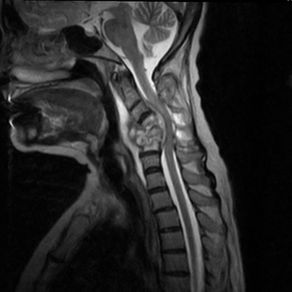

Case #8: інтрамедулярний об’ємний утвір на рівні C6-C7